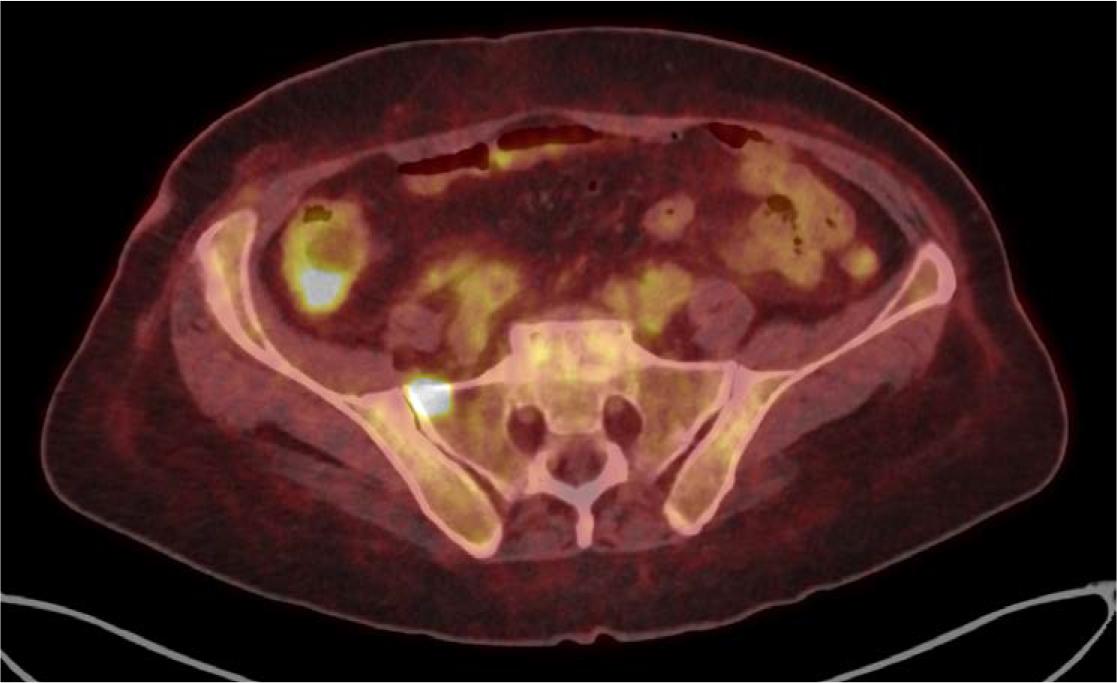

[18F]FDG PET/CT, axial plane – the image shows focal increased uptake in the sacral bone. The uptake did not correspond with any suspicious lesions in the contrast-enhanced CT examination performed later. Increased radiotracer uptake in the cecal wall is also visible, with thickening of the intestinal wall on the non-contrast CT.